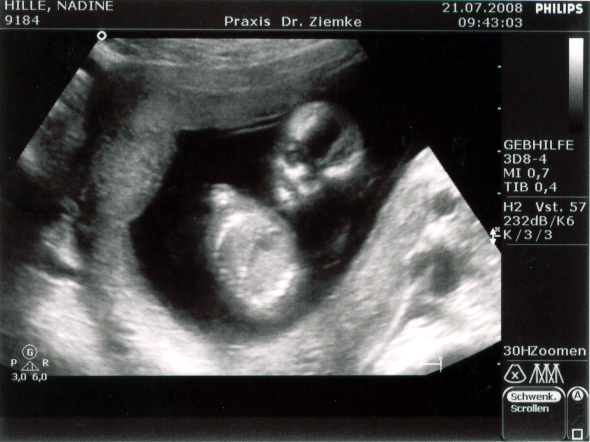

Vorhin waren wir bei Nadins neuer Frauenärztin in der Tuchmacherstraße – Annika Stellmacher heißt die. Und die schreibt nun die Fortsetzung von Nadins Mutterpass. Auf der ersten Seiten des zweiten Teils steht:

21.7. | SSW (LR) 14/4 | SSW korrigiert 13/4

SSL 6,9 | BPD 2,3

Und übersetzt heißt das, dass Nadin nicht in der 15. Schwangerschaftswoche ist, sondern erst in der 14.. Somit verschiebt sich der voraussichtliche Gerburtstermin eine Woche nach hinten – und zwar auf den 22. Januar 2009.

SSL steht für Scheitel-Steiß-Länge, und die beträgt jetzt 6,9 cm.

BPD steht für Biparietaler Durchmesser, und der ist entsprechend 2,3 cm.

Zusammenfassend bedeutet das: Alles in bester Ordnung. Das Herz schlägt, die Anzahl der Finger ist korrekt. Und Mehrlinge werden es auch nicht…